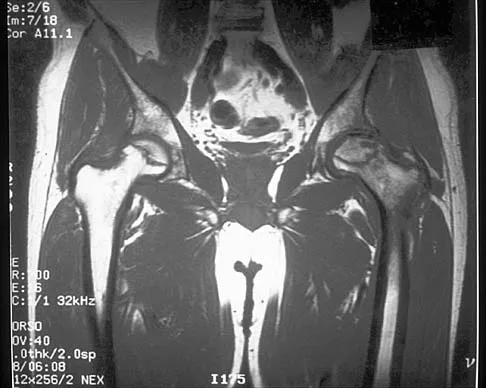

Figure 41 shows the MRI scan of a 39-year-old man who has severe left groin and anterior thigh pain. What is the most likely diagnosis?

Explanation

A 46-year-old woman has bilateral groin pain, with more severe pain on the left side than on the right side. Figures 44a and 44b show a radiograph and a T1-weighted MRI scan. What is the most likely diagnosis?

Explanation